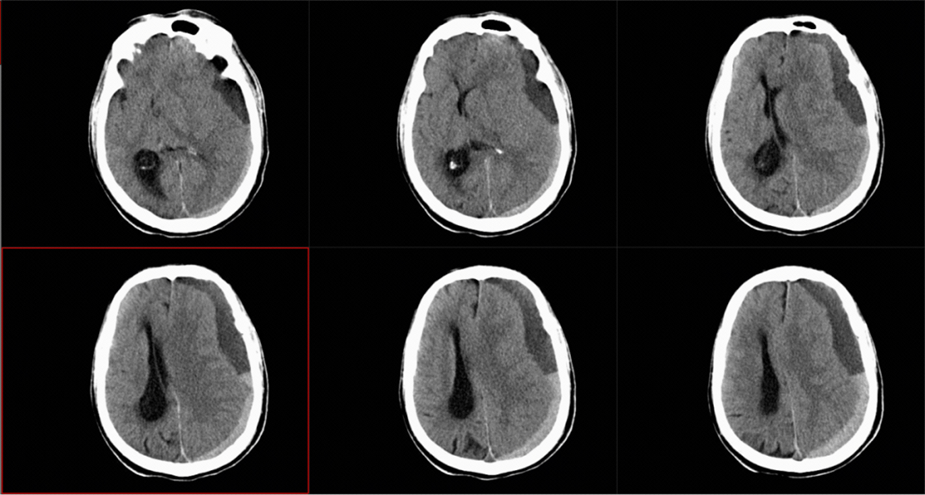

经过CT检查,医生诊断张老先生患的是“慢性硬膜下血肿”。(图1)

图1 急诊CT影像,见左侧硬膜下混杂慢性硬膜下血肿,中线受压右移。